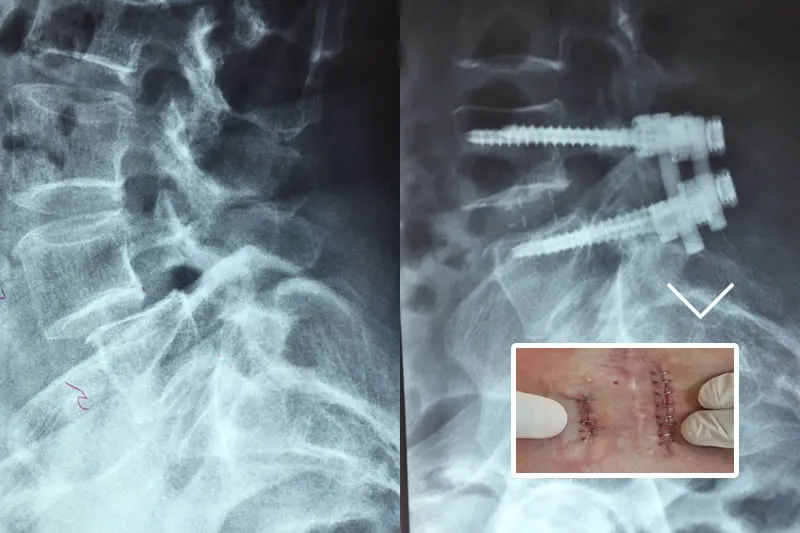

The simple X-rays in AP and Lateral projection that we carry out are complementary tests and will allow us to rule out other types of pathologies, since the findings that we can find in them (decreased disc height, bone growths in the vertebral margins, scoliosis, etc.) are also appreciated in patients without any type of lumbar pain.

Treatment for low-back pain usually depends on whether the pain is acute or chronic. In general, surgery is recommended only if there is evidence of worsening nerve injury and when diagnostic tests indicate structural changes for which corrective surgical procedures have been developed.

Surgery: When other treatments fail, surgery may be considered an option to relieve pain caused by severe musculoskeletal injury or nerve compression. It may be months after surgery before the patient recovers completely and may suffer a permanent loss of flexibility. Surgical procedures are not always successful and there is a lack of evidence to show which procedures work best for the problem for which they are indicated.